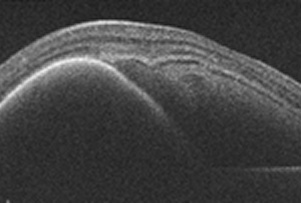

습성 황반변성

이 부위에 변화가 생기면 중심 시력이 떨어져 글씨가 흐려 보이거나 직선이 휘어져 보이는 증상이 나타나는데, 이를 황반변성이라고 합니다.

사물이 휘어보인다. 중심시야가 어둡거나 보이지 않는다.